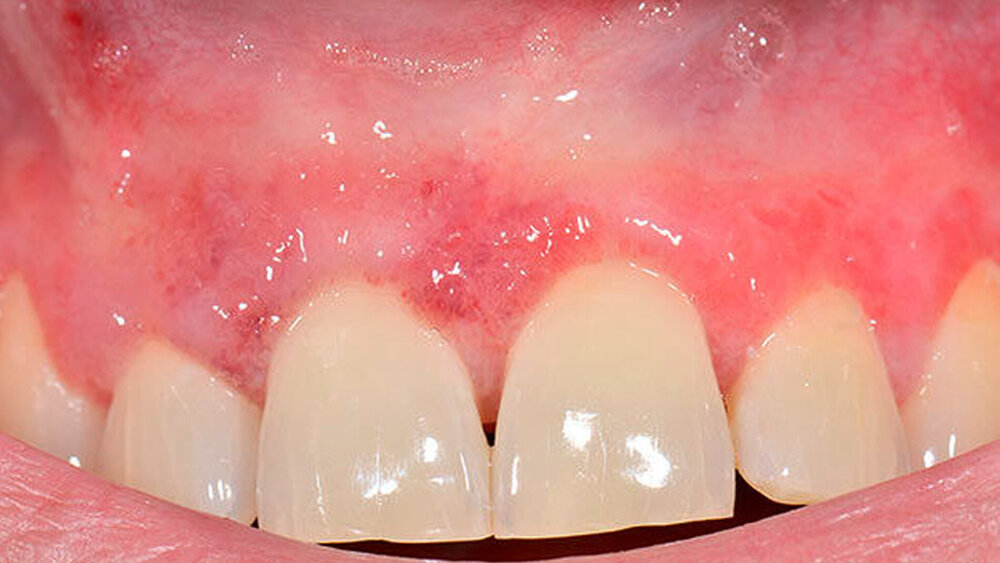

Neben der beschriebenen Läsion fanden sich oral leicht hyperplastische, papulöse Veränderungen der Gingiva vestibulär und palatinal ohne Hinweise auf Ulzerationen (Abbildungen 1 und 2). Vom klinischen Aspekt war der Befund daher gut vereinbar mit oralen Veränderungen infolge eines Morbus Crohn. Weiterhin gab der Patient eine Rötung an der Glans penis an. Der letzte Versuch einer MRT-basierten Dünndarmuntersuchung sowie einer Koloskopie und Gastroskopie scheiterte 2016 an der Compliance des Patienten.

Zur Diagnosesicherung bei der oralen Läsion empfahlen wir eine Probeentnahme der Mundschleimhaut sowie weiterführende serologische Untersuchungen. Die Stanzbiopsien des Gaumens und der vestibulären Gingiva erbrachten den histologischen Nachweis von oberflächlich perivaskulär gelegenen, kräftig lymphozytären, granulomatösen Infiltraten und passten somit zu einer mukokutanen Manifestation des bekannten Morbus Crohn. Serologisch ließen sich bis auf eine Vitamin-B12-Negativbalance, die in der Folge substituiert wurde, keine Auffälligkeiten nachweisen, insbesondere keine Autoantikörper.

Die Therapie bestand daher initial nach Abschluss der Wundheilung aus lokalen Steroiden zunächst als Applikation von Triamcinolonacetonid (Volon-A-Haftsalbe) sowie einer begleitenden antimykotischen Therapie mit Amphotericin-B-Lutschtabletten (Ampho Moronal; 3 x d). Bei fehlender Wirksamkeit der Haftsalbe erfolgte bei einem Nachsorgeintervall von zwei Monaten die Umstellung auf ein höherpotentes Glukokortikoid (Clobetasol). Unter dieser Medikation zeigte sich ein schneller Rückgang der Beschwerden und der oralen Manifestation des Morbus Crohn (Abbildung 3).